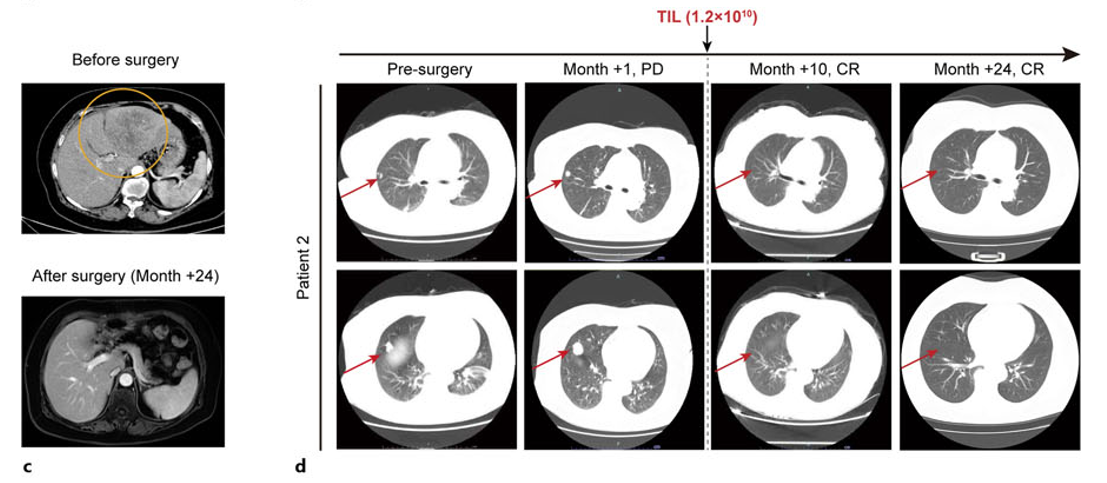

对于许多晚期实体瘤患者来说,在看到CAR-T细胞疗法有效缓解血液系统肿瘤患者的病情时,需要新疗法的心变得更加迫切。2024年,首款用于实体肿瘤的TIL疗法终于获美国食品药品监督管理局(FDA)批准上市,成为近年来最具潜力的实体瘤治疗技术之一。